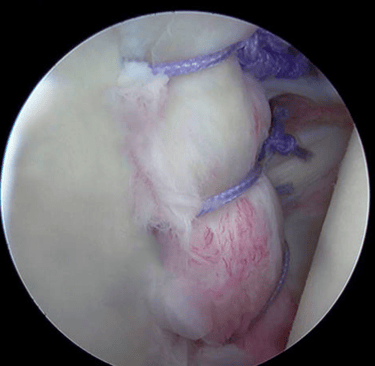

La artroscopia de hombro es un procedimiento quirúrgico mínimamente invasivo que permite diagnosticar y tratar diversas afecciones dentro de esta articulación. A través de pequeñas incisiones, el especialista introduce una cámara diminuta (artroscopio) y herramientas especiales para visualizar y reparar los tejidos dañados sin necesidad de abrir completamente el hombro.

La artroscopia se realiza en quirófano, bajo anestesia regional o general. A través de incisiones milimétricas, se introduce el artroscopio para explorar el interior del hombro y se utilizan instrumentos quirúrgicos especiales para reparar los tejidos según sea necesario. Al tratarse de una técnica mínimamente invasiva, los tiempos de recuperación son menores en comparación con la cirugía abierta.